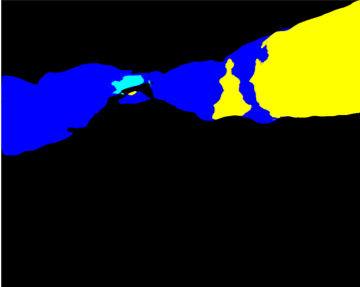

Our challenge was made up of 3 sub-problems. The first was binary instrument segmentation, where each frame was separated into da Vinci Xi instruments and a background class, which contained an ultrasound probe, surgical clips and porcine tissues. The second task was instrument part segmentation, where we scored the participants on whether they could correctly segment each articulating part of the instrument (see Fig. 3). Our final task was to segment and classify the instruments (see Fig. 4).

We provided the first 225 frames of 8 sequences as training data and kept the last 75 frames of those 8 sequences as test data. 2 of the full 300 frame sequences were kept as test sequences. Test labels were kept hidden from the participants. Our datasets contain 7 different robotic surgical instruments. The Large Needle Driver, Prograsp Forceps, Monopolar Curved Scissors, Cadiere Forceps, Bipolar Forceps, Vessel Sealer and additionally a drop-in ultrasound probe, which is typically held in the jaws of the Prograsp Forceps instrument. Samples from the training datasets are depicted in Fig. 2 and examples of the different instrument types are shown in Figure 3 and 4.